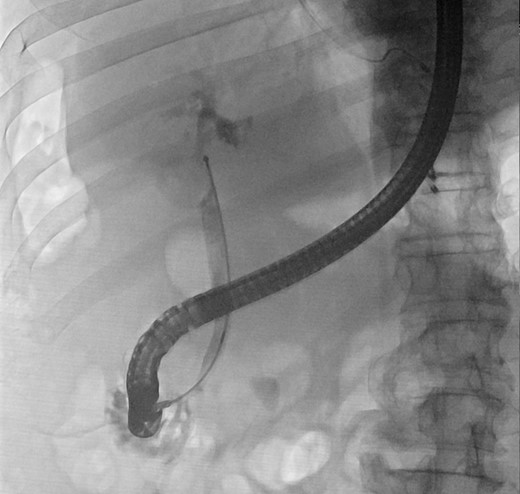

In view of his multiple medical comorbidities, which included obesity, hypertension, hyperlipidemia, ischemic heart disease with history of percutaneous transluminal coronary angioplasty, obstructive sleep apnea and sick sinus syndrome, he was considered a poor candidate for definitive surgery. Therefore, after the index cholangitic episode had settled, he received further endoscopic treatment. A combination of endoscopic papillotomy, biliary stenting and mechanical lithotripsy (ML) was adopted. After a total of eight additional sessions of ERCP, with repeated stent exchange, stone clearance was achieved. He was well and discharged with cleared ducts. Long-term stenting was not required.

Our case illustrates a patient with type II Mirizzi syndrome successfully treated with conventional endoscopic techniques in ERCP. Stone clearance was achieved mainly through repeated sessions of mechanical lithotripsy with plastic stenting. This technique is more familiar to the standard endoscopists, and expensive instruments are not required, providing an alternative means of treatment and stone removal for patients with type II Mirizzi but who are not suitable surgical candidates. Notwithstanding this, more extensive research has to be carried out to guide the optimal care in difficult bile duct stones.